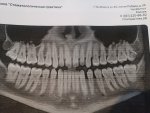

Ну ебало моё представляешь, пока с одной стороны делают жуешь другой стороной, и тут ещё одна дырка на зубе. Ну не пиздец а? С обеих сторон по 1. Началась та же ипопея кто мне сделает сейчас а не через месяц. Сделали, 3 часа сидел, и успели временную пломбу поставить которая на следующий день вылетела

Вот по итогу, рот болит, зубы болят, минус 20 тыс, пью еду.